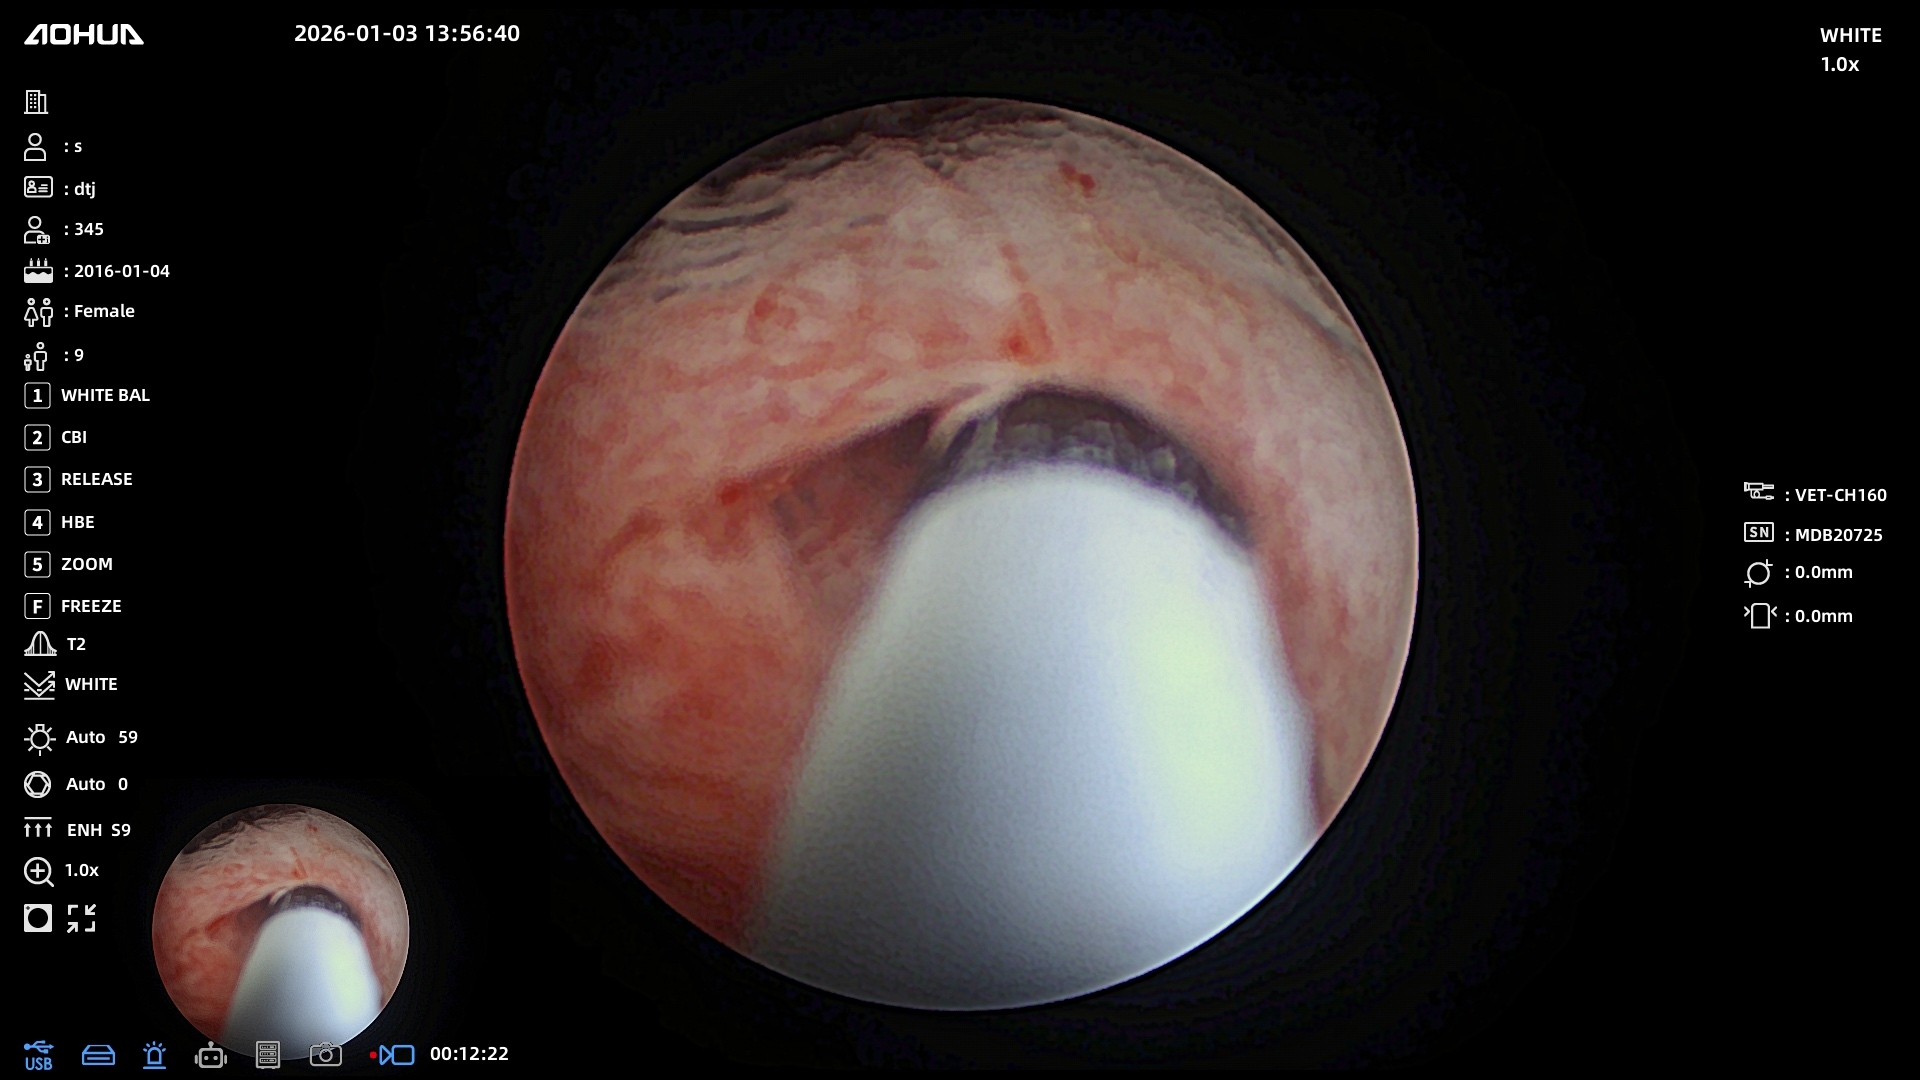

Нас тепло приняли в Эндовет, провели все необходимые обследования и на следующий же день была назначена операция. Нашей таксе почти 10 лет, опасались, как она перенесет наркоз. Но после беседы с Александром Владимировичем стало спокойнее. Операция длилась 3 часа, были удалены камни из почек и мочеточника, установлены стенты. Все прошло более чем хорошо. 2,5 дня стационара, 2 небольших прокола, собака чувствует себя хорошо и быстро восстанавливается. Большое спасибо команде клиники, анестезиологу, работникам стационара, регистратуры и, конечно же, Александру Владимировичу за такой тяжёлый и нужный труд. До сих пор не верится, что мы дома и все закончилось благополучно благодаря Вам)